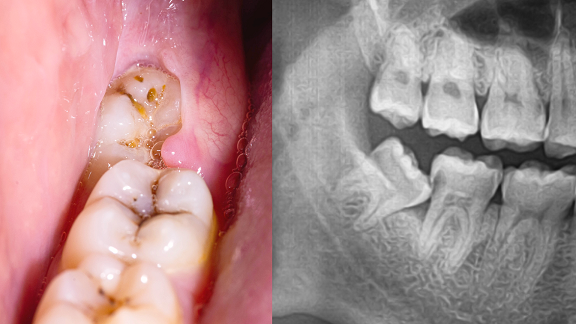

Endodontic Infection

About Root Canal Treatment

Root canal treatment may be recommended when the soft tissue inside a tooth (pulp) becomes damaged or infected, which can occur due to decay, trauma, or other causes. If left untreated, such conditions may lead to discomfort or further complications.

During the procedure, the dentist removes the affected tissue from inside the tooth, cleans and disinfects the area, and fills the space with a sealing material. In some instances, additional steps may be taken to address concerns such as tooth discolouration.

Endodontic treatment

This treatment option may help retain the tooth and restore its function. Your dentist will assess your condition and discuss whether root canal therapy is appropriate in your case.